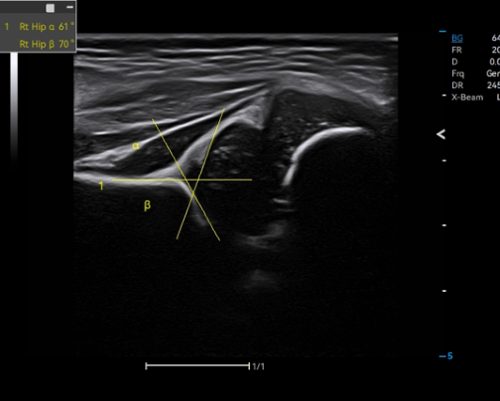

· Auto Hip provides reliable evaluation of hip dysplasia by automatic identification of bone and cartilage baseline and top line, along with measurement of α and β angles.